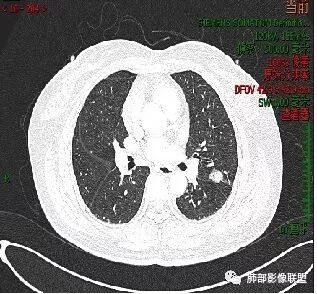

看看这个。左边为什么会胸膜往上?因为左边是GGO为主,右边是比较实,就占位效应出来,所以凸出来了心灵鸡汤:@岳微-辽宁省朝阳234医院-影像诊断 应该是心包隐窝初学者:如是炎症,是同步发生,首先边缘不会有边界清楚的GGO,慢性炎症应该连渗出都很少了,更加不会有一部分是收缩,一部分是膨隆

南边:有边界清楚GGO吗张玉:有南边:有就好办边界清楚MGGO,分叶、胸膜凹陷

大家好像意见一致,腺癌那就考虑腺癌

晨读结果:病理是微浸润腺癌